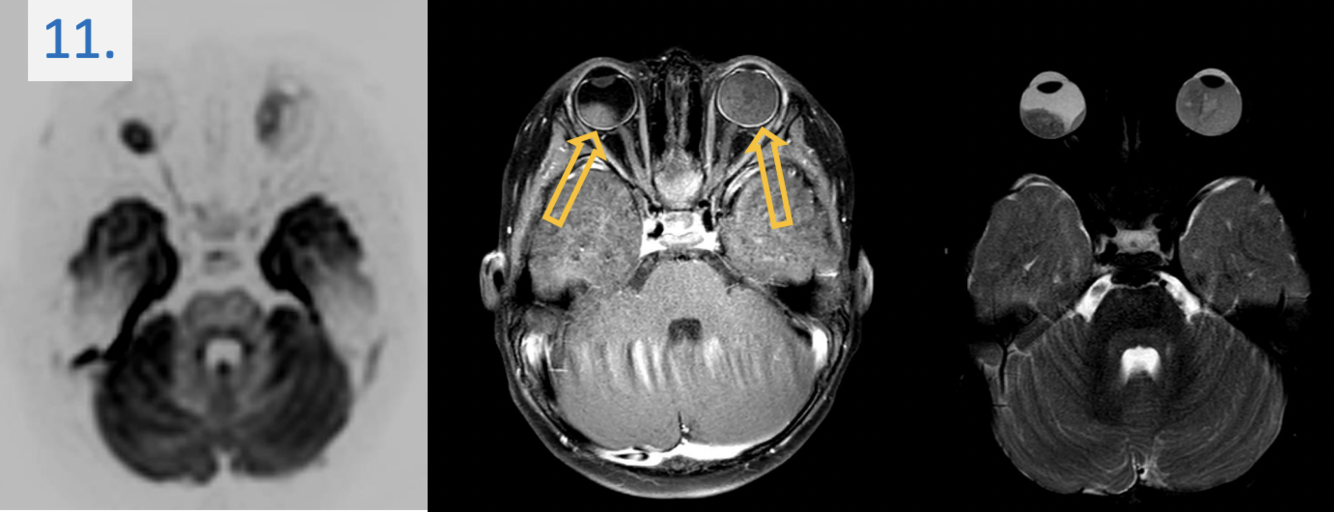

11.